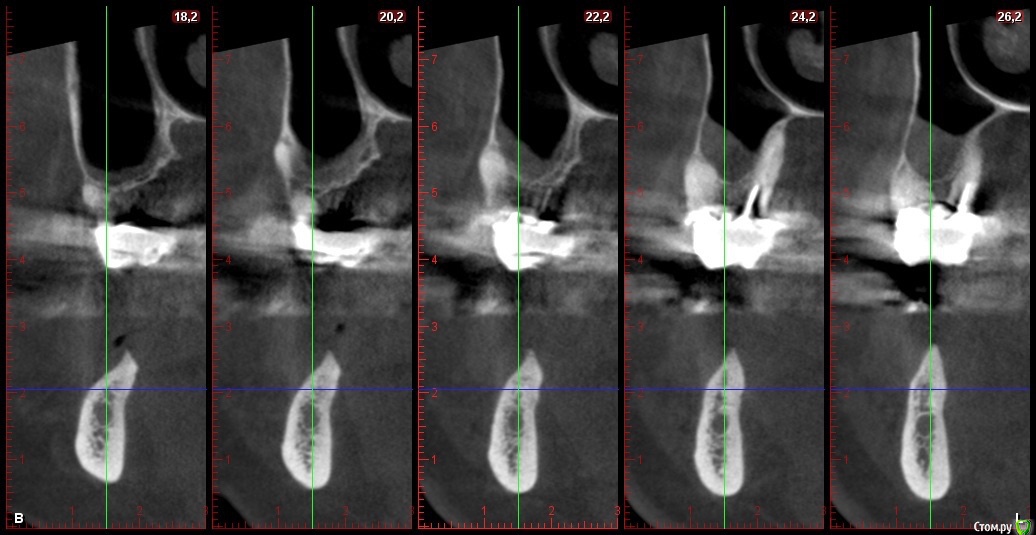

Глеб Митрофанов Опубликовано 22 октября, 2015 Автор Поделиться Опубликовано 22 октября, 2015 Срезы кт Ссылка на комментарий

basha.ru Опубликовано 23 октября, 2015 Поделиться Опубликовано 23 октября, 2015 Спасибо за кейс.Скажите пожалуйста какая высота кости до нижнечелюстного канала?Спасибо. Ссылка на комментарий

Глеб Митрофанов Опубликовано 23 октября, 2015 Автор Поделиться Опубликовано 23 октября, 2015 (изменено) Спасибо за кейс.Скажите пожалуйста какая высота кости до нижнечелюстного канала?Спасибо.До канала , в самой низшей точке - 4,5-5 мм Изменено 23 октября, 2015 пользователем Глеб Митрофанов Ссылка на комментарий